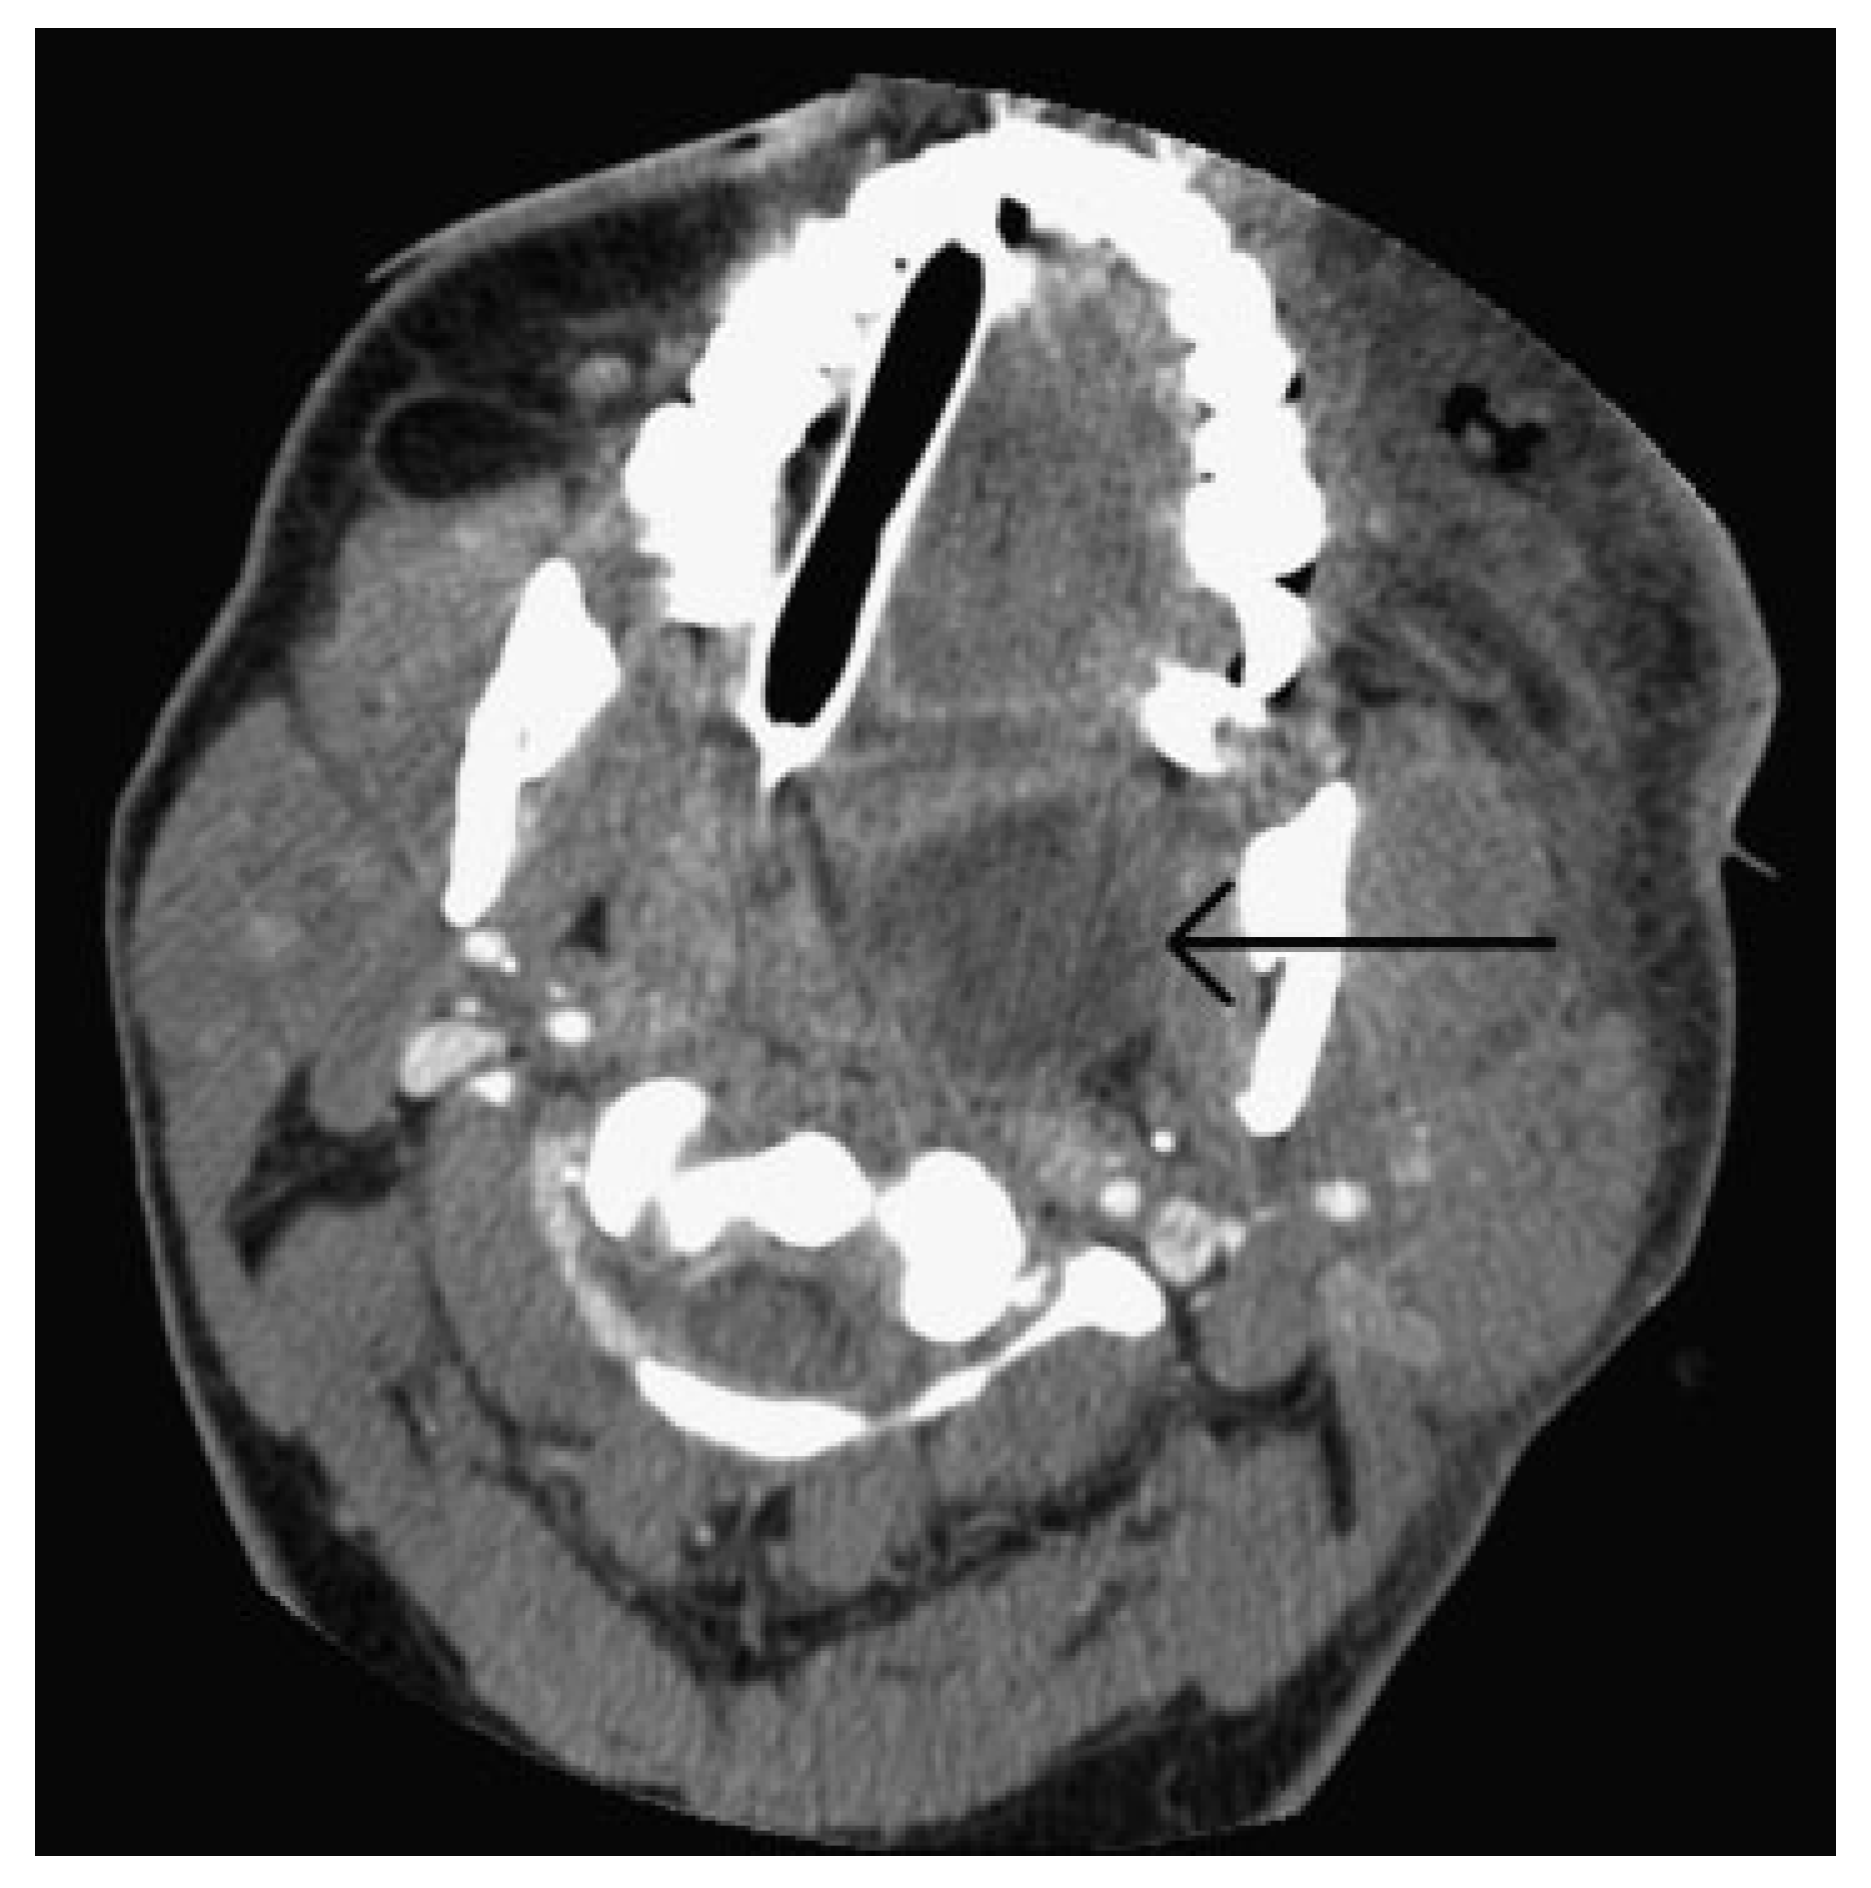

The patient was taken immediately to the operating room due to her worsening clinical presentation and the authors’ suspicion for necrotizing soft tissue infection. Incision and drainage and debridement of the necrotic tissue were performed on the left periorbital, zygomatic, and temporal regions (►Figure 3A–D). Copious purulent drainage was obtained which was submitted for Gram stain and cultures. Irrigation of the wound was then performed until no further murky fluid was appreciated with approximately 5 L of 0.9% normal saline. The wound was then packed in a standard wetto-dry fashion. The patient was placed on vancomycin, piper-acillin/tazobactam, and metronidazole and transferred to the intensive care unit (ICU) where she remained intubated and sedated. In the ICU, she was supported medically, including optimization of her blood glucose. Overnight, the patient remained tachycardic and febrile with a maximum temperature of 103°F (39.4 °C). At that time, a maxillofacial CT with contrast was obtained, which revealed left periorbital, orbital, and buccal inflammatory changes. Proptosis, lateral and downward displacement of the globe, and homogeneous opacification of the frontal, ethmoid, and maxillary sinuses were appreciated on the left side. The right ethmoid sinus was partially opacified, which justified the inflammatory changes in the right orbit. Additionally, a large fluid loculation of the left lateral pharyngeal space was present (►Figure 4). The intraoral examination revealed a large localized swelling of the left oropharynx and nasopharynx, with deviation of the palatal uvula from the midline. Ophthalmology was reconsulted. On postoperative day 2, the patient was taken back to the operating room for incision and drainage of the left maxillary sinus and left lateral pharyngeal space and washout of existing wound. An intraoral incision was made on the left posterior oropharynx and blunt dissection was performed to enter the left lateral pharyngeal space where approximately 15 mL of purulence was obtained and samples were sent for cultures and sensitivities. Three nonrestorable, grossly carious left maxillary posterior teeth were then extracted to negate any possible source of odontogenic infection; however, no purulence or periapical involvement of the teeth was evident upon extraction. This made an odontogenic cause of the infection unlikely. The left maxillary sinus was entered via a standard Caldwell-Luc approach to drain the fluid collection appreciated on CT and an additional 5 to 10 mL of purulence was obtained. After copious irrigation of the sites, two ½ inch Penrose drains were placed, one in the left maxillary sinus and the other in the left lateral pharyngeal space. The drains were then secured to the oral mucosa with sutures. Washout and redressing of the left periorbital wound was then performed and the patient returned to the ICU intubated. Laboratory values showed white blood cell count of 15.9 g/dL, hemoglobin of 12 g/dL, hematocrit of 36.4%, and platelet count of 226,000/µL. Chemistry showed sodium level of 134 mmol/L, potassium level of 3.5 mmol/L, chloride level of 97 mmol/L, bicarbonate level of 27 mmol/L, blood urea nitrogen level of 6 mg/dL, creatinine level of 0.7 mg/dL, and glucose level of 375 mg/dL. Hemoglobin A1C was 12.8 and C-reactive protein was 34.2 mg/dL. The patient’s previously recorded hemoglobin A1C was 13.0 recorded 26 months earlier at the medicine clinic showing long-term poor diabetic control. Over the next few days, the patient clinically improved and her vital signs stabilized with the exception of a persistent elevated temperature of 101°F. Cultures came back as group C β hemolytic Steptococcus and Proteus mirabilis. After consultation with the infectious disease service, the antibiotics were narrowed to ampicillin/sulbactam and clindamycin. A repeat CT scan was obtained on hospital day 5 and a loculation was noted at the superior and lateral aspect of the left orbit, suggestive of subperiosteal abscess (►Figure 5A,B). Ophthalmology service recommended no intervention for the left orbital subperiosteal abscess. However, as the patient was still having low-grade temperature of 101°F (38.3 °C), the authors took the patient back to the operating room for incision and drainage of this area. We approached the superior-lateral orbit via an existing incision, and approximately 5 mL of purulence was obtained. Postoperatively, the patient improved clinically, and became afebrile. The intraoral drains were removed, and after cons ultation with the wound nurse, the wet-to-dry dressing of the skin was changed to petroleum-impregnated gauze. Despite our objection, the patient remained intubated for a prolonged period due to the discomfort of the ICU team in extubating the patient. The patient was extubated on hospital day 12. On the day of discharge, examination revealed significant decrease in left periorbital swelling, decrease proptosis, and increase extraocular movement in all directions; however, she continued to have 20/400 vision in the left eye and diplopia. Due to the defect in the left upper and lower eyelids, a home care nurse was assigned for daily dressing changes. Intraoral examination demonstrated resolution of swelling of the oropharynx. A maxillofacial CT scan revealed resolution of the original fluid loculations and a patent airway. Throughout the postoperative hospital stay, the patient’s glucose level and blood pressure were controlled. The patient was discharged on hospital day 13 with oral antibiotics, amoxicillin/clavulanic acid, and clindamycin, as well as her home antihypertensive and diabetic medications. The patient was closely followed up and her condition continued to improve. At 4 months follow-up, the patient presented with resolution of facial swelling; had proptosis and eyelid ptosis, normal extraocular movements; and her baseline visual acuity of her left eye remained 20/400. The patient was seen 1 year postoperatively and had continued resolution of her wounds with appropriate wound closure; however, she had continued strabismus, ptosis of the upper and lower lid secondary to scar contraction, as well as left V2 paresthesia (►Figure 6A,B). The orbital wound continued to heal via secondary intention with anticipated reconstruction and scar revision in the near future.

Figure 4. Axial computed tomographic scan showing the involvement of the left lateral pharyngeal space. Arrow shows well loculated abscess in the lateral pharyngeal space.